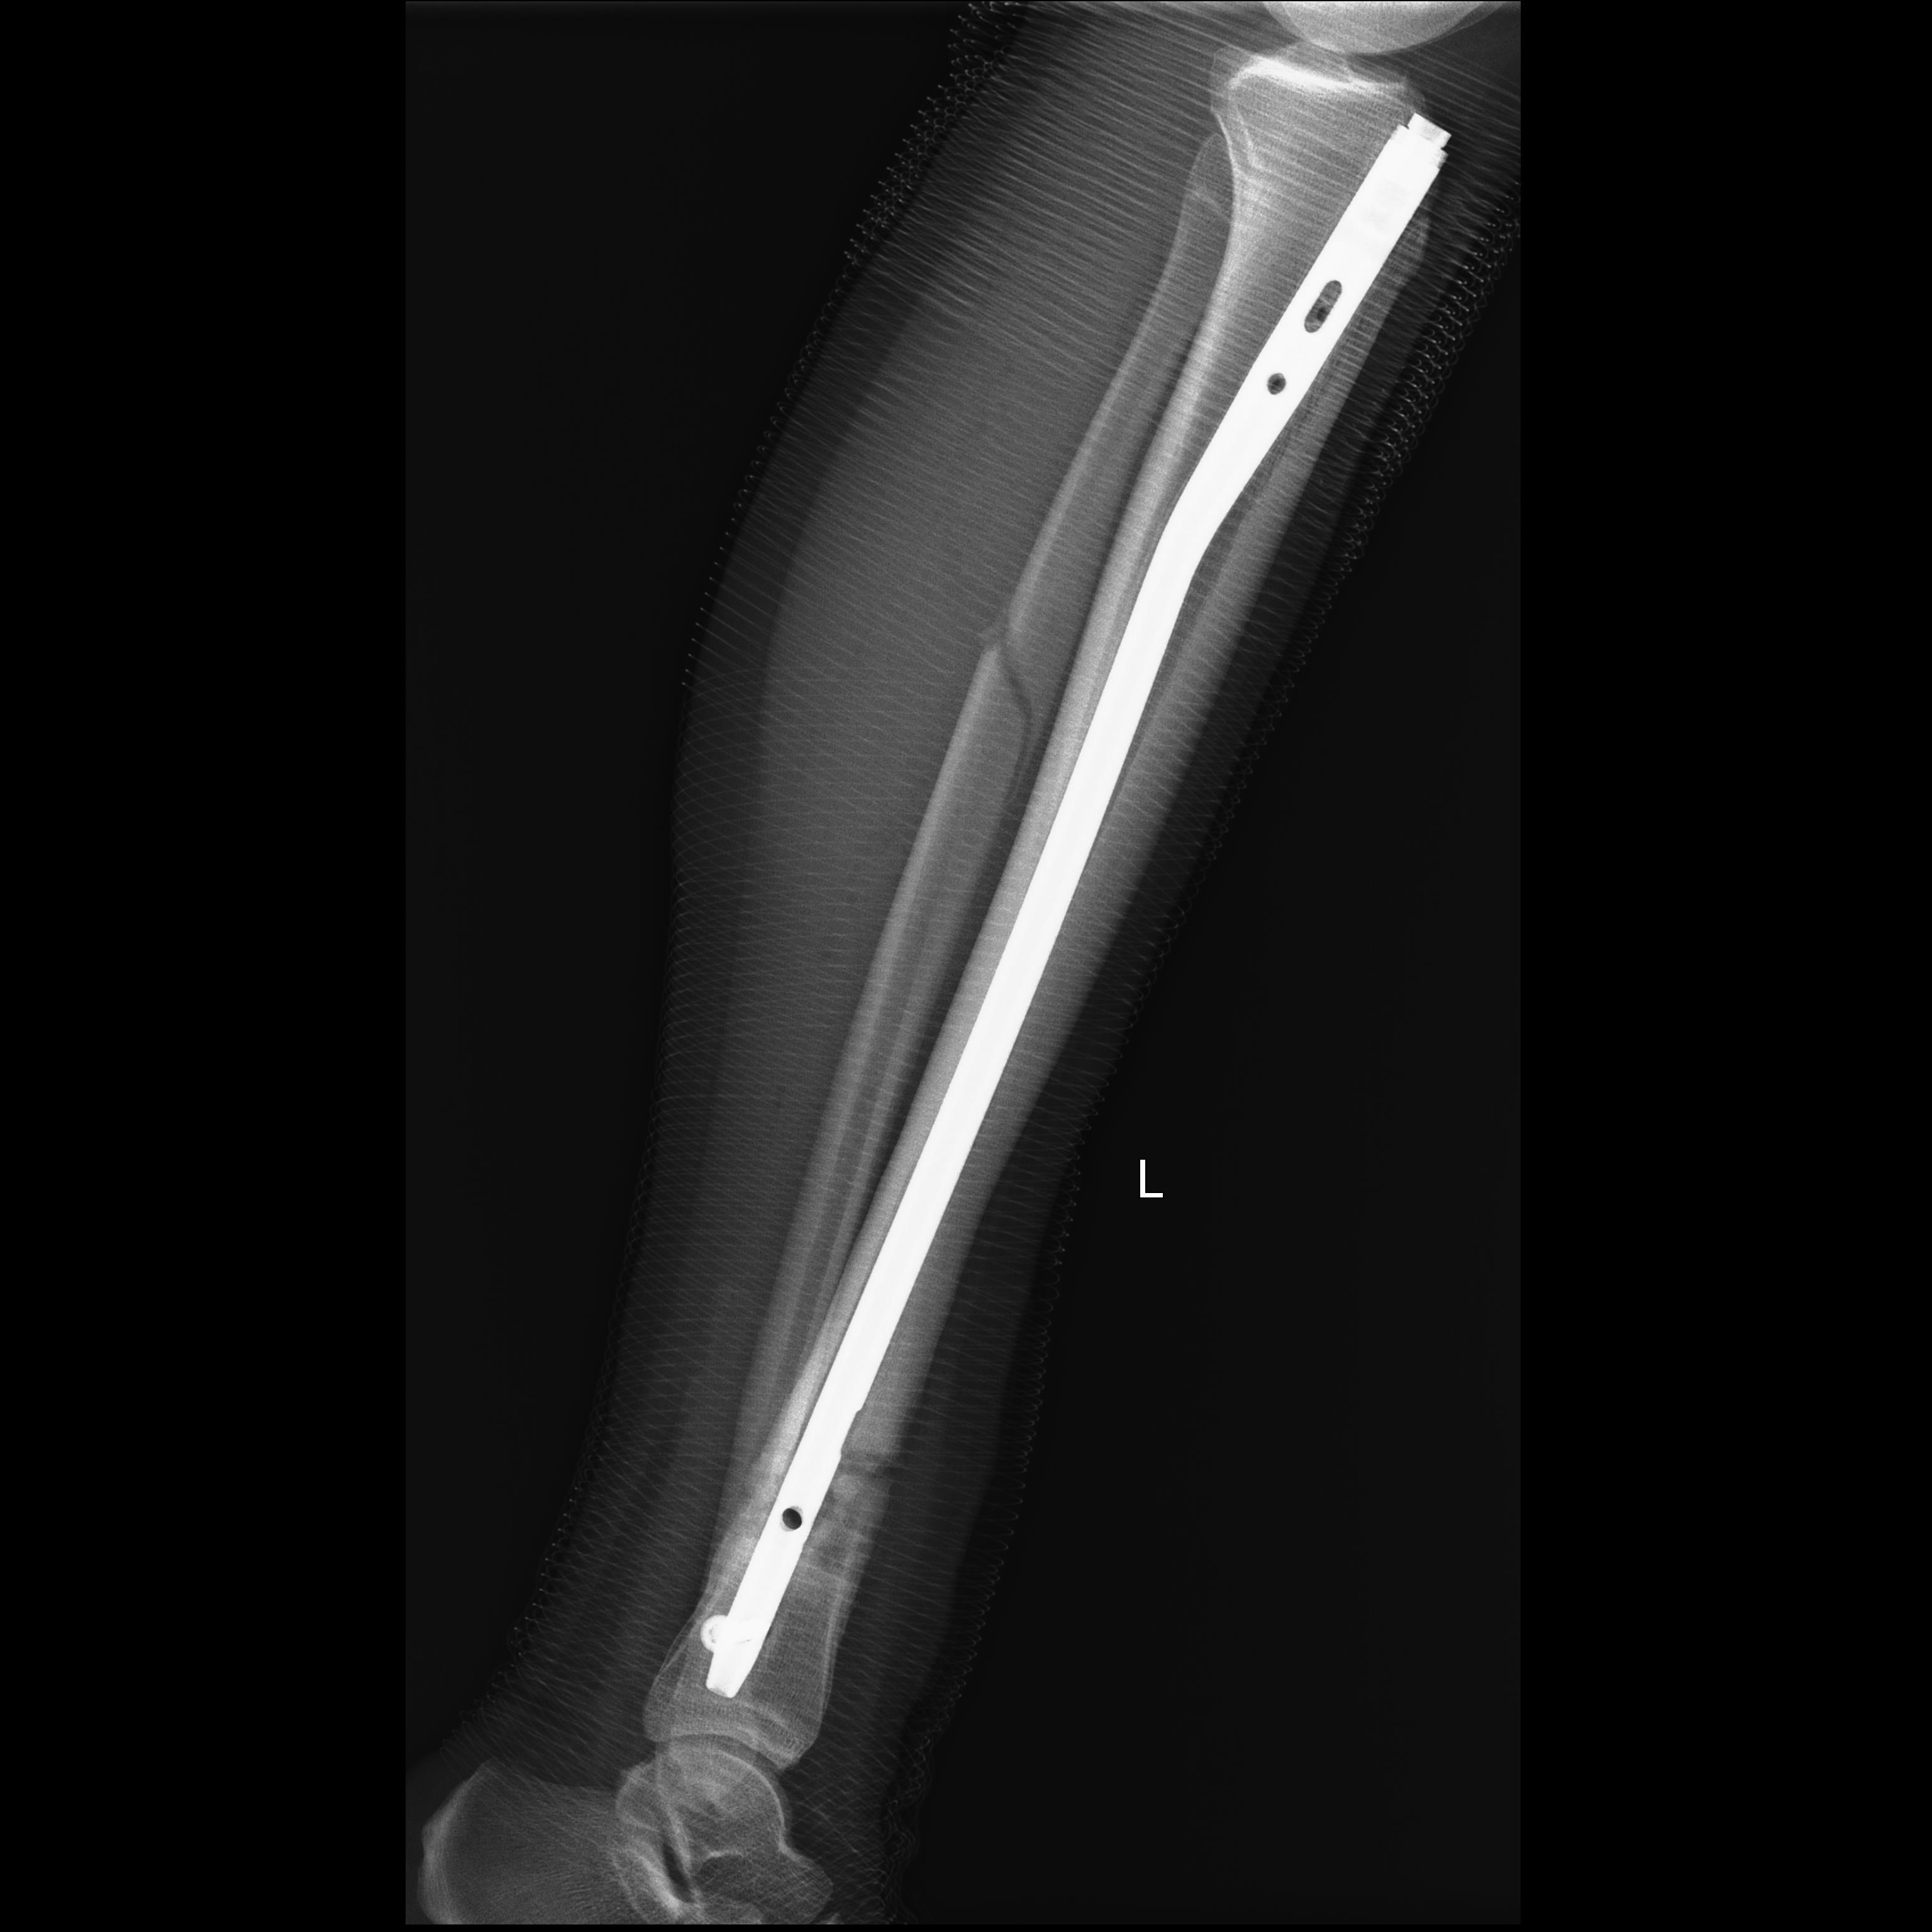

Контроль через 6 недель

Клинических жалоб нет, голень незначительно больше в объеме со здоровой стороной. Передвигалась с палочкой, режим нагрузки расширен до полного

Контроль через год от последнего вмешательства. Перелом консолидирован. Спасибо за поддержку и критику